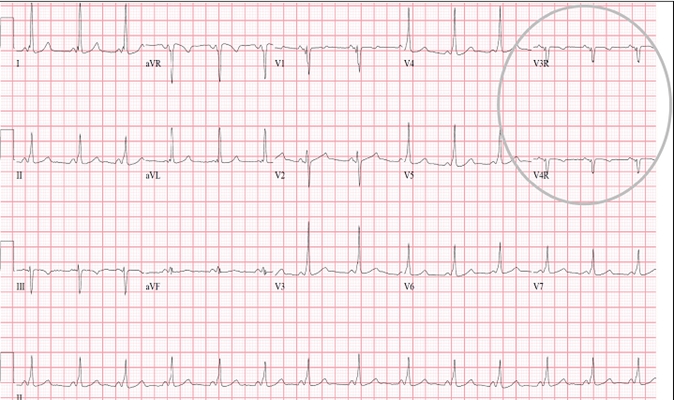

預激綜合徵心電圖 (9)

A:預激綜合徵典型的心電圖表現是竇性心搏的PR間期縮短,短於0.12s,而且導聯的QRS波群時間超過0.12s。QRS波群起始部分會有粗鈍,終末部分正常,甚至會導致ST-T波型呈現繼發性的改變,甚至於QRS波群主波方向相反。預激綜合徵是指心房……

A:預激綜合徵是很少見的心律失常,是房室傳導異常的一種類型,提早興奮心室的一部分或全部,引起心室肌提前激動,常合併室上性心動過速。心電圖可見PR間期縮短小於0.12秒;QRS時限延長0.11秒以上;QRS波群起始部粗鈍,繼發性ST-T改變。沒有……

A:預激綜合徵合併房速的時候,心電圖可以出現快速而且寬大畸形的QRS波群,有點類似於室性心動過速,典型的預激波有可能會被覆蓋。合併房速的時候會有極快速的心室率、QRS波群會寬大畸形,也有可能比較易變和複雜。患有預激綜合症合併房速,如果有明顯的心……